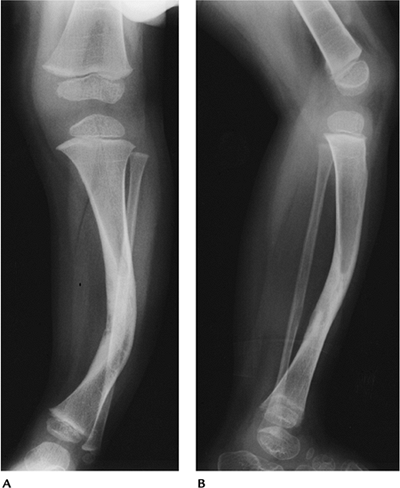

FIGURE 15-14 Neurofibromatosis Type 1. AP (A) and lateral (B) radiographs showing tibial bowing with a healed midtibial fracture.

|